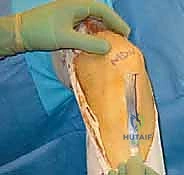

الخطوة الأولى: الفحص بالمنظار الجراحي 4K

يستخدم الدكتور